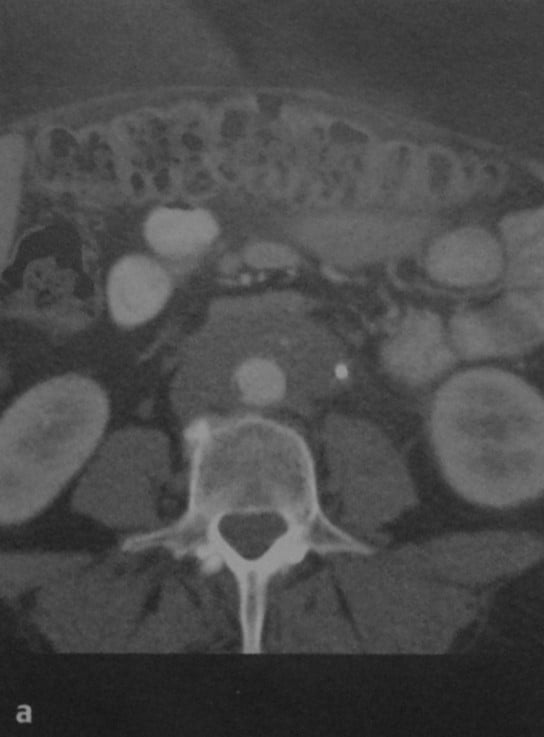

КТ ретроперитонеального фиброза: Изображения и диагностика